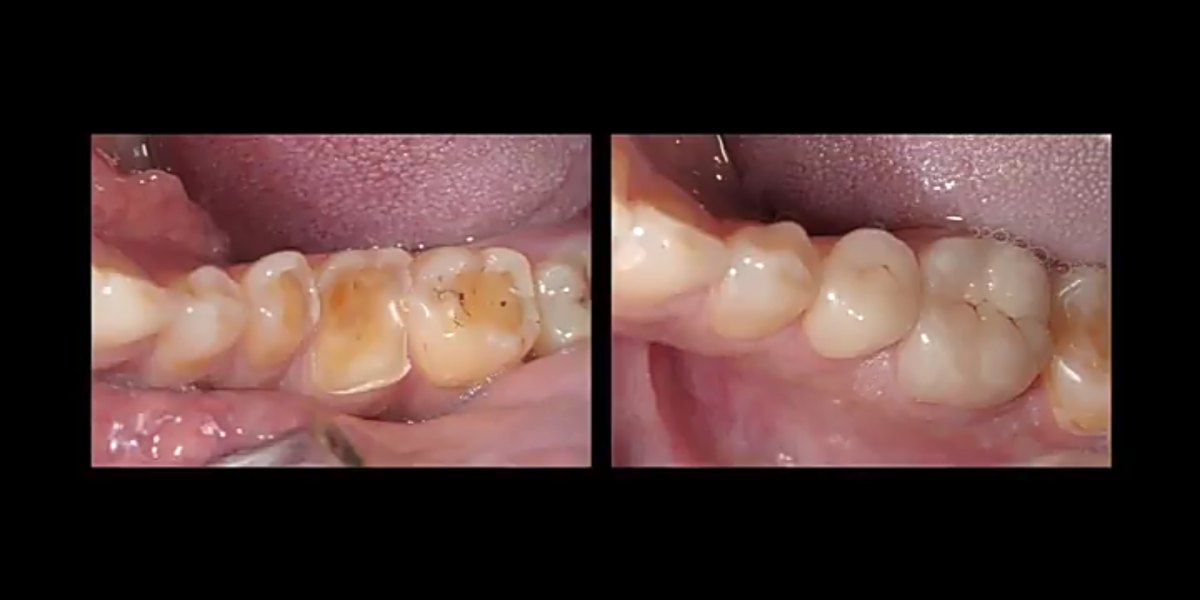

W naszym Centrum stomatologicznym w Lublinie leczenie rozpoczynamy od ustalenia przyczyny starcia zębów. W tym celu przeprowadzamy kilkuetapowe badanie diagnostyczne, zwane deprogramacją Koisa. Polega ona na znalezieniu i rejestracji tzw. Relacji Centralnej, czyli takiego położenia żuchwy, które jest niezależne od działania mięśni. (Gwarantuje nam ono długoczasowe, bezawaryjne funkcjonowanie wykonanej rekonstrukcji zwarcia). W kolejnym etapie analizujemy i oceniamy zwarcie pacjenta na modelach gipsowych w artykulatorze i planujemy leczenie. Przy niewielkim stopniu starcia zębów często postępowanie sprowadza się do korekty zwarcia. W zaawansowanym stopniu konieczna jest odbudowa utraconych tkanek zębów. Stosowane są tu metody zachowawcze (odbudowa specjalnym, dedykowanym materiałem kompozytowym o twardości równej do twardości szkliwa) oraz metody protetyczne tzn. onlye, licówki, korony.

Albo nadbudowujemy zęby materiałem do odbudowy zwarcia (specjalny kompozyt o twardości i śieralności równej tkankom zęba) lub wykonujemy licówki okluzyjne ceramiczne. Leczenie prowadzone jest najczesciej po procesie deprogramacji aby efekt był możliwie jak najbardziej trwały od 250- kompozyt, do 2000- lic. cyrconowa kompozyt- na 1 wizycie, Licówka- kilka dni nieStarte zęby jak odbudować?/Jak zregenerować starte zęby? ▶